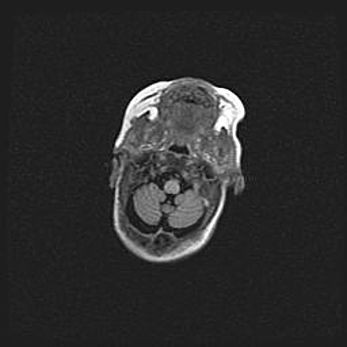

Лейкомаляция с кистозно-глиозной дегенерацией головного мозга.

Возраст: 2 месяца 25 дней

Вес: 6400 г

Окружность головы: 40 см

Срок гестации: 41 неделя

Лейкомаляцию относят к ишемически-гипоксическим повреждениям головного мозга, диагностируемым у новорожденных. При лейкомаляции в головном мозге обнаруживают очаги некроза, возникшие после тяжелой гипоксии и нарушения кровотока. В процессе морфогенеза очаги проходят три стадии: 1) развития некроза, 2) резорбции и 3) формирования глиозного рубца или кисты. Перивентрикулярная лейкомаляция (ПЛ) встречается примерно в 12% случаев среди новорожденных, обычно – у недоношенных детей, причем, частота ее зависит от массы, с которой младенец появился на свет. Наибольшее число малышей страдает лейкомаляцией, если масса при рождении 1500-2500 г.